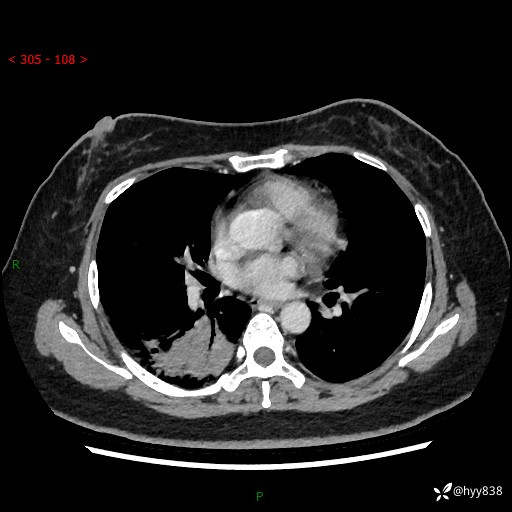

胸部CT平扫